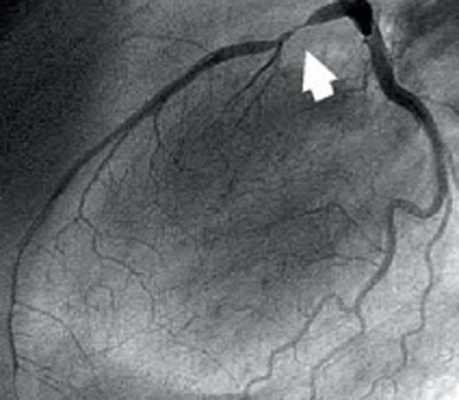

Представлены коронарные артерии в латеральной проекции.

- Левая главная или левая коронарная артерия (ЛКА)

- Левая передняя нисходящая артерия (ЛПН)

- диагональные ветви (D1, D2)

- септальные ветви

- краевые ветви (M1,M2)

- Ветвь острого края (ОК)

- Ветвь АВ-узла

- Задняя нисходящая артерия (ЗНА).